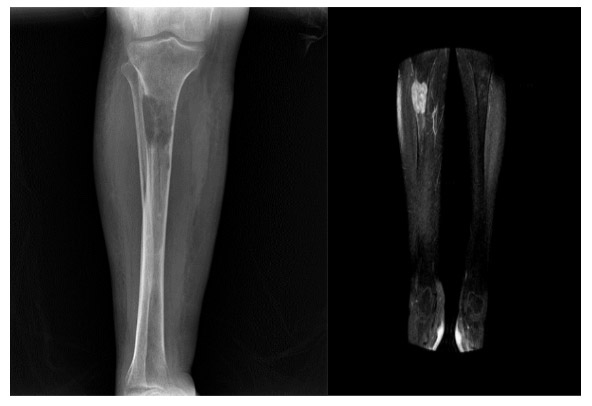

CASE 48: Breast cancer increases the risk of fracture due to metastasis to the upper end of the right tibia (shinbone).

Before the surgery: X-ray shows damage/destruction and risk of fracture in the upper outer part of the right tibia, while MRI shows tumor tissue in the same location.